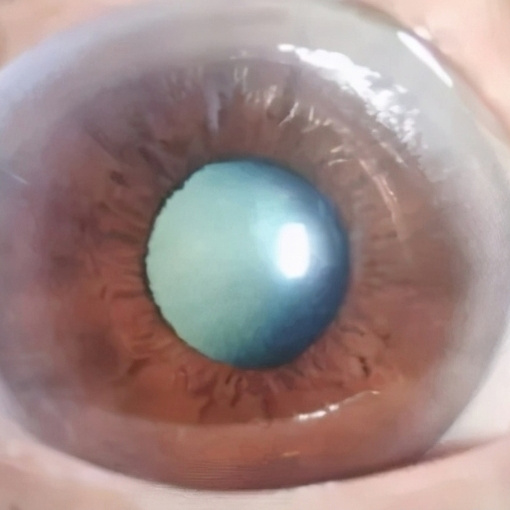

白内障超声乳化摘除术+人工晶体植入术

超声乳化技术具有切口小,手术时间短、术后散光少,术后恢复快,并发症少,与过去传统白内障手术方式相比,不用等到白内障成熟了才能手术,大多数患者在手术后的第二天就能恢复到满意的视力水平。

白内障和正常眼